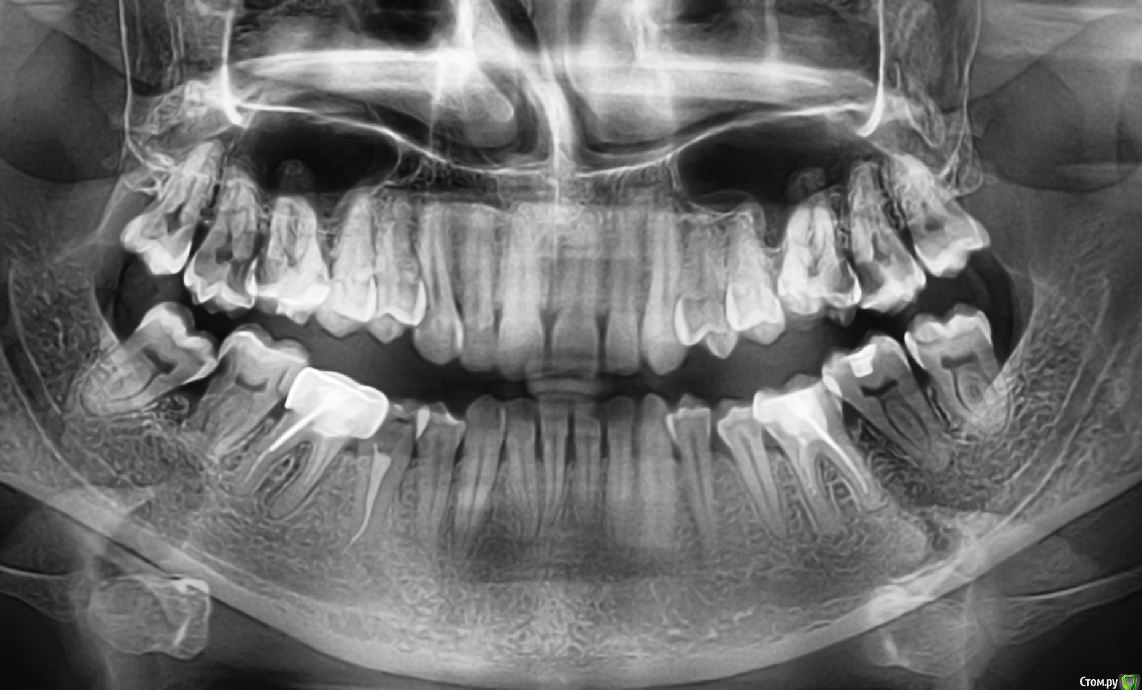

vicTORYa Опубликовано 24 мая, 2016 Поделиться Опубликовано 24 мая, 2016 Здравствуйте.В сентябре 2015 года лечила зубы с правой стороны.Снимок до леченияЛечили нижние 4,5,6,7,8 и верхние 3,4,5,6,7,8 зубы справа. В 5 и 7 верхних зубах случилась перфорация пазухи, врач поставил ультракал на месяц. Остальные зубы запломбировал постоянными пломбами, в каналы гуттаперчю поставил.В октябре пришла долечить 5 и 7 зубы. 5 запломбировали, а в 7 обнаружилась перфорация корня, врач запломбировал этот перфорированный канал какой-то специальной пастой (названия не помню). Два верхних и три нижних подготовил под коронки. Коронки решили ставить позже.Всё ждала, когда боль пройдет, но в некоторых зубах она так и не прошла, на тот момент при нажатии на зубы или постукивание болели 5, 6, 7 верхние (кажется 8 тоже), нижний 7 и немного ныл 5 нижний. Сделала панорамный снимок и пошла к врачу, он направил к ЛОРу так как увидел пятно в пазухе.Снимок на тот моментЛОР послал на КТ пазух.Сказал, что это кистозно-полипозное образование и его нужно удалять.Так ничего и не делала, оставила ситуацию в подвешенном состояние так как я в полной растерянности.На данный момент болят при постукивание верхние 5,6,7, 8 но совсем немного, при нажатие 6,7. Нижний 7 болит при нажатий и постукивание, немного 5 (и как будто ноющая боль бывает).Свежий снимок.Помогите пожалуйста разобраться. Что с этими зубами? Почему они продолжают болеть? Насколько большая проблема материал, выступивший за предел корня? Нет ли вокруг него воспалительного процесса? И что мне с ними делать дальше? Одевать ли коронки? Или может какие-то из них вообще подлежат удалению? Что с пазухой? Если нужны какие-то другие срезы из КТ могу выложить. Заранее спасибо. Ссылка на комментарий

Паращук Роман Опубликовано 24 мая, 2016 Поделиться Опубликовано 24 мая, 2016 В верхних зубах материал за пределами корня и скорее всего в пазухе. Может стать причиной воспалительных процессов или усугубить их,или поддерживать. В нижней 7ке выведенная гуттаперча за пределы канала. Если есть проблемы,то их нужно решать или организм решит их за вас. В верхних зубах эндоскопически через носовой ход,в нижнем попробовать через каналы,если нет хирургически. Ссылка на комментарий